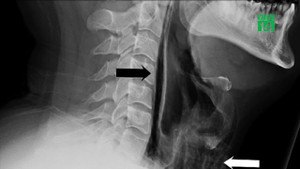

Áp suất quá lớn trong hệ hô hấp khi nhịn hắt hơi sẽ khiến không khí lưu chuyển tới tai một cách đột ngột. Với áp suất mạnh như vậy, tai giữa và màng nhĩ sẽ bị ảnh hưởng, trong một số trường hợp, màng nhĩ của bạn thậm chí có thể bị thủng.